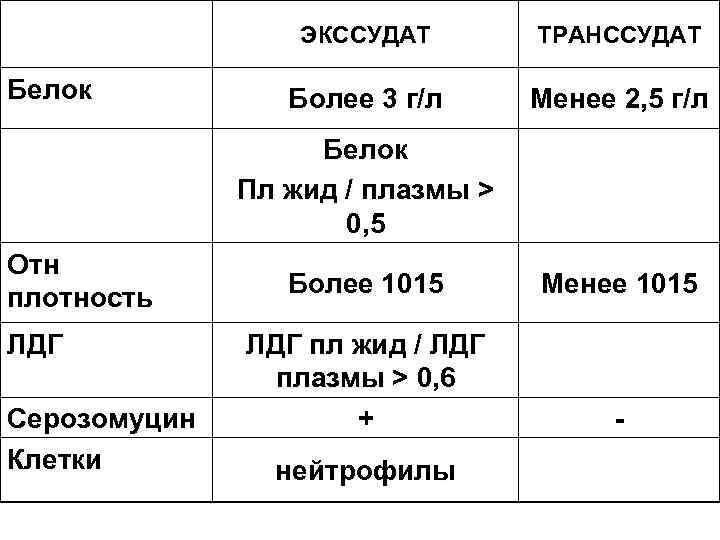

ЭКССУДАТ Белок ТРАНССУДАТ Более 3 г/л Менее 2, 5 г/л Белок Пл жид / плазмы > 0, 5 Отн плотность ЛДГ Серозомуцин Клетки Более 1015 Менее 1015 ЛДГ пл жид / ЛДГ плазмы > 0, 6 + - нейтрофилы